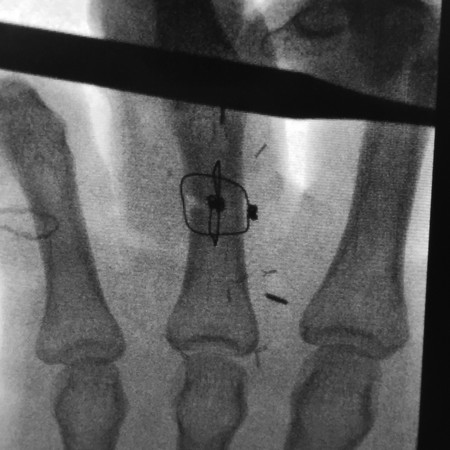

Fig. 12.15 Radiograph of box wires.

Fig. 12.18 Completed intraoperative 90–90 box wiring.